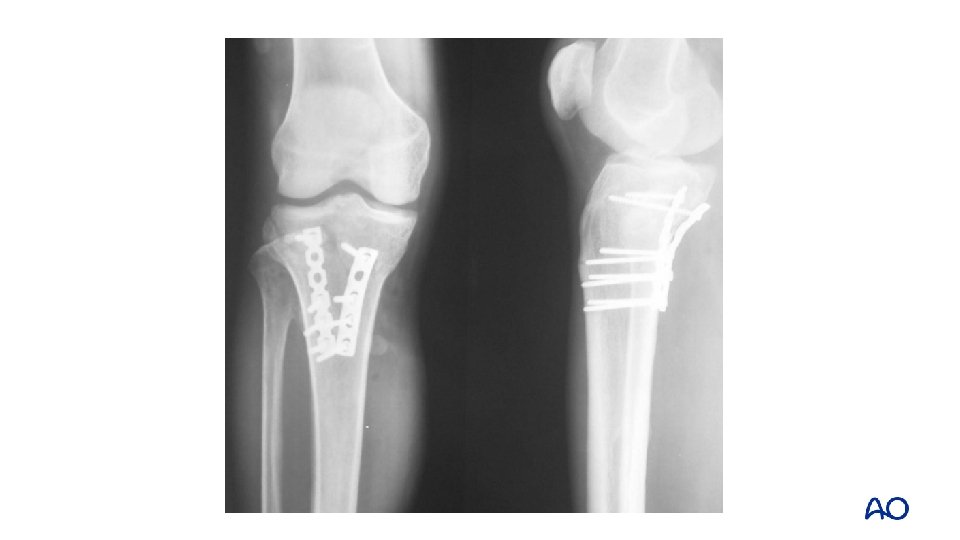

Schatzker type IV: 2 -column fracture—flexion varus Varus flexion mechanism medial posterior

Approach: midline and posteromedial

Midline approach Fracture window Posteromedial approach

1 -year follow up